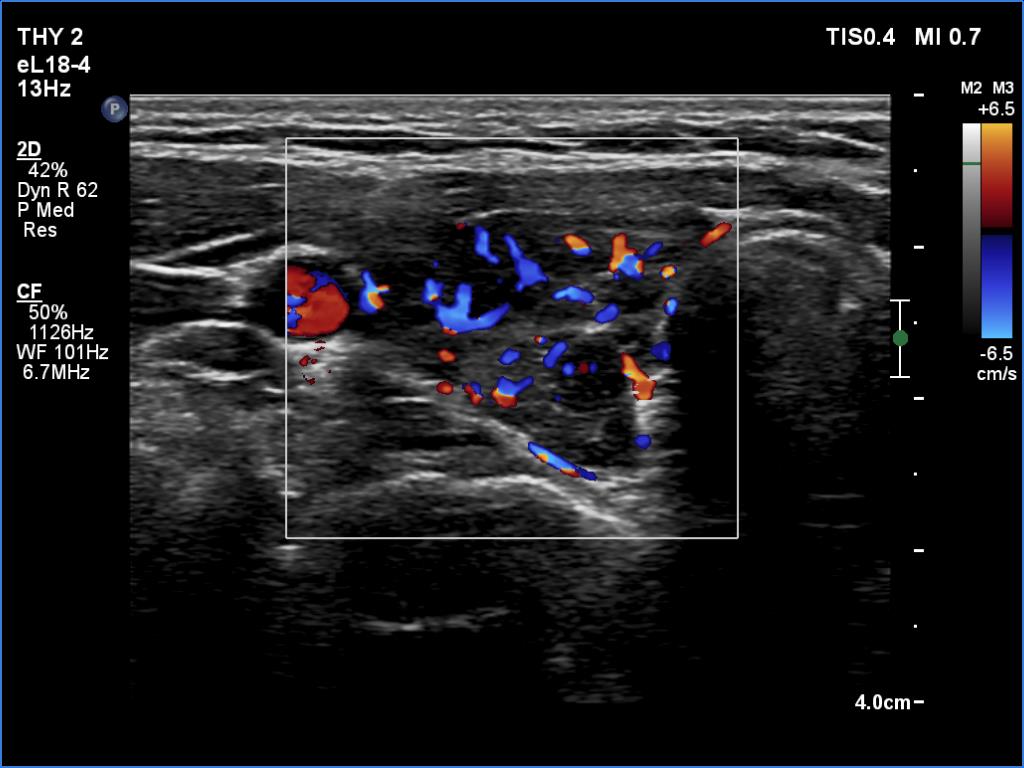

Second examination a year later (second row of images):

Comment. The patient presented a post partum thyroiditis, i.e., the underlying autoimmune thyroiditis became more active. The change in ultrasound pattern is also in line with this. Be aware the rapid change in ultrasound pattern. In other cases, the echogenicity can change in years, rather decades in the case of a hypothyroidism. The structure is expected to show the pattern seen in the first study a year later.Clinical data: Half a year ago, the patient gave birth. She took 100 microgram of medicine a day in the second half of the pregnancy, and after giving birth she returned to the previously used dose of 50 micrograms a day. She gained 8 kg in the last three months and had other symptoms which suggested underdosing.

Palpation: unchanged.

Laboratory tests: TSH 9.88 mIU/L, FT4 7.61 pM/L on daily 50 microgram levothyroxine.

Ultrasonography. In contrast to the previous examination, the entire thyroid became hypoechoic. There were only small islets with less hypoechoic pattern.

Suggestion: to increase the dose of levothyroxine to daily 75 micrograms. Repeat TSH in 6 months.